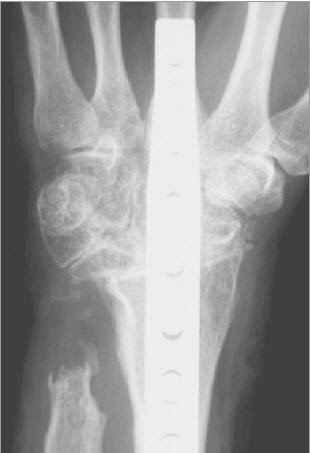

Totale Handgelenkversteifung

Sind alle Kompartimente des Handgelenks zerstört, wie dies bei der rheumatoiden Arthritis oder nach Unfällen recht häufig der Fall ist, bleibt lediglich die Versteifung des gesamten Handgelenks. Das Handgelenk lässt sich nach verschiedenen Verfahren versteifen, welches je nach Arthrosetyp und Knochenqualität ausgewählt wird.

Die operative Fixation wird in der Regel mit Platten, Schrauben oder Spezialnägeln erreicht. In den seltenen Fällen grosser Knochendefekte als Folge einer erheblichen Gelenkzerstörung ist es angezeigt, Knochen vom Beckenkamm zu entnehmen und am Handgelenk anzulagern.